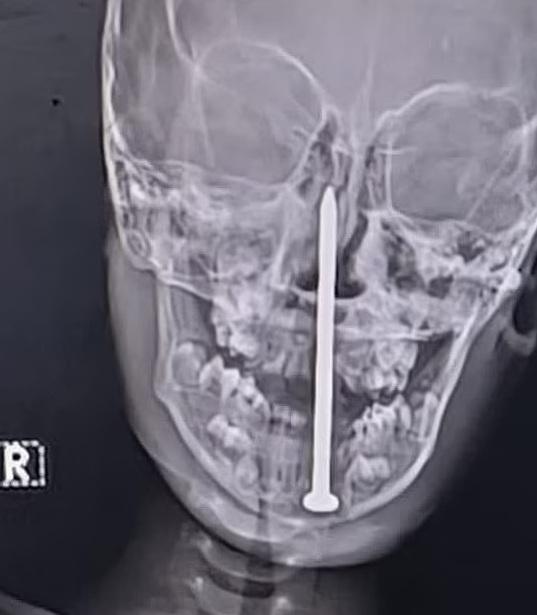

X光檢查顯示,8厘米長鐵釘從下顎進入,直插男童腦部。(互聯網)

北方邦勒克瑙喬治國王醫學大學(King George's Medical University)創傷外科主任蒂瓦里表示,經磁力共振及電腦掃描檢查後發現,當時鐵釘尖端已深入男童的腦部,距離主要血管相當近,情況十分危急。但他也驚嘆,鐵釘剛好能避開腦部這條主要血管,「實在是奇蹟」。